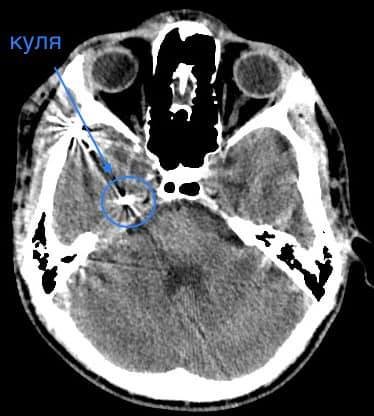

У Волинській обласній дитячій клінічній лікарні прооперували 16- річного юнака з травмою головного мозку. І травма ця дуже незвичайна – у хлопця була куля в голові, що призвела до руйнації скроневої кістки та частини головного мозку.

Лікарі виконали невідкладну операцію і вилучили стороннє тіло, видалили пошкоджені тканини і відновили цілісність збережених тканин.

«Добре, що куля зупинилась в 1 см від надзвичайно важливої судини і права скронева частка (яка пошкодилась в результаті травми) - функціонально незначима. Інакше, наш козак був би зовсім іншим, навзавжди», - пише лікар.